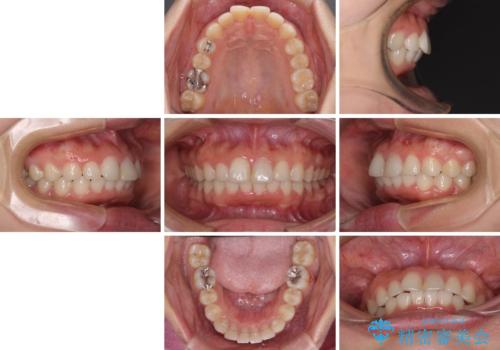

矯正治療の後戻り ガタガタになった前歯の部分矯正

- 以前の矯正治療の後戻りを気にして来院された患者様です。

下顎前歯にデコボコがあるため、ワイヤー矯正により改善することとしました。

もう少しデコボコを改善したかったのですが、ご本人の希望もあり、装置を除去しました。

後戻りを防止するため、舌側を細いワイヤーによる保定を行いました。